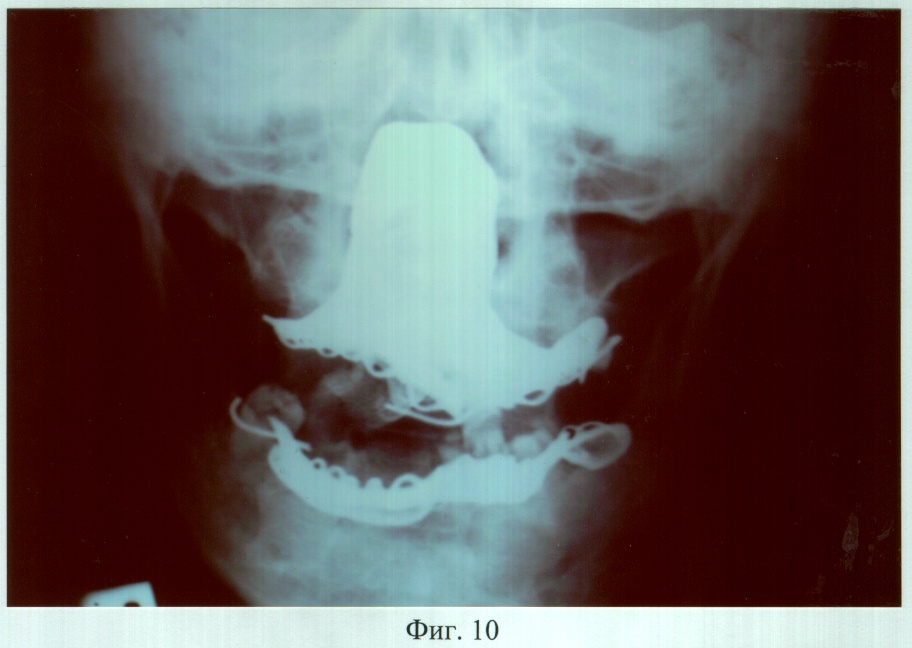

На фиг.10 – рентгенограмма больного М. через 3 года после ортопедического лечения (прямая проекция).

Адаптация к протезам наступила в течение семи дней, после чего больной отмечал удовлетворительное функциональное состояние зубочелюстного аппарата. Фонетическое обследование с помощью разработанного способа диагностики нарушений речевой функции (заявка на изобретение №2005104063, Россия: МКИ А61В 5/00, 5/12, А.А.Радкевич, В.Г.Галонский, приоритет от 15.02.2005 г.), включающее оценку произношения звуков и разборчивости речи (гнусавости) с помощью карты-опросника, с последующим математическим вычислением процента нарушения, показало, что до ортопедического лечения нарушено произношение звуков – б, в, д, з, и, к, л, м, р, т, х, ш, щ; k (коэффициент разборчивости речи) = 5; U (величина нарушения речевой функции) = 41,2%. После протезирования нарушено произношение звуков – д, л, т, ш, щ; k=3; U=8,7%. При осмотре через 2 года больной жалоб не предъявлял, состояние протезов удовлетворительное. Морфологические исследования слизистой оболочки протезного ложа и рентгенография костей лицевого скелета, проведенные до и через 6, 12, 24 и 36 месяцев после протезирования, показали отсутствие признаков воспаления и прогрессирования атрофии.

Адаптация к протезу наступила в течение семи дней, после чего больная отмечала удовлетворительное функциональное состояние зубочелюстного аппарата. Фонетическое обследование показало, что до ортопедического лечения нарушено произношение звуков – г, ж, к, п, р, т, ц, ч; k=5; U=21,3%. После протезирования нарушено произношение звуков – г, ж, к, р, ц; k=3; U=6,6%. При осмотре через 3 года больная жалоб не предъявляла, состояние протеза удовлетворительное. Морфологические исследования слизистой оболочки протезного ложа и рентгенография костей лицевого скелета, проведенные до и через 6, 12, 24 и 36 месяцев после протезирования, показали отсутствие признаков воспаления и прогрессирования атрофии.

С использованием данной технологии проведено ортопедическое лечение 5 больных, в возрасте от 26 до 63 лет. Адаптация к ортопедическим конструкциям протекала в сроки от 7 до 14 дней, после чего больные отмечали удовлетворительное функциональное состояние зубочелюстного аппарата. Во всех случаях получен удовлетворительный эстетический результат. Последующие клинические наблюдения в сроки 6, 12, 18, 24, 36 месяцев после протезирования не выявили функциональных нарушений, отзывы о протезах удовлетворительные. Анализ морфологических исследований слизистой оболочки протезного ложа до и в отдаленные сроки после ортопедического лечения позволил сделать вывод об отсутствии воспалительных явлений и признаков прогрессирования атрофии. Рентгенологических признаков дальнейшей атрофии костной ткани протезного ложа, связанной с протезированием, не выявлялось ни в одном случае. Сравнительные результаты фонетической диагностики и исследований жевательной эффективности по С.Е.Гельману между больными, протезирование которым выполнено конструкциями, изготовленными предложенным способом и традиционными, представлены соответственно в таблицах 1 и 2.